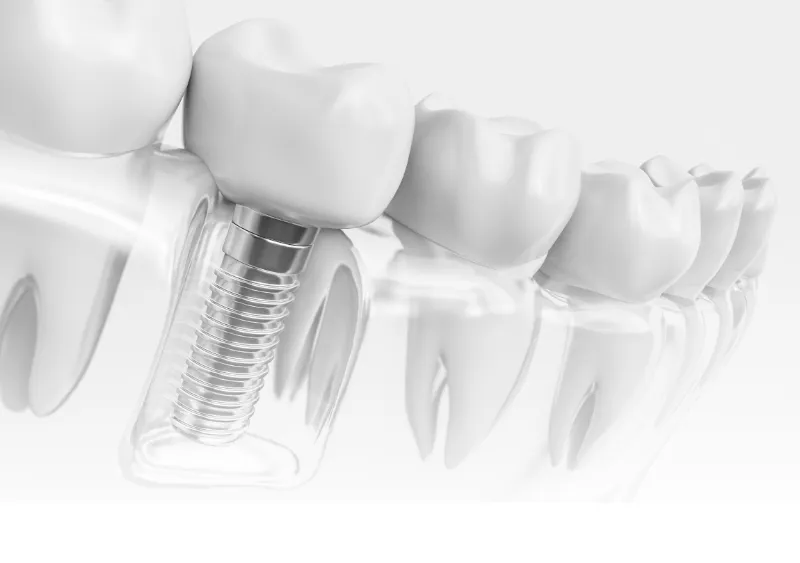

歯が抜けたところの顎骨にインプラント(人工歯根)を埋入し、そこに上部構造(人工歯)を装着する治療です。抜けた歯の代わりとなる治療には入れ歯やブリッジもありますが、インプラント治療は自費診療となるので価格が高くなります。それでもインプラント治療が多くの人に選ばれるのには、機能性や審美性の高さ、将来的に長く噛めるなどのさまざまなメリットがあるからだと考えられます。

インプラントを骨に埋めることでしっかり固定され、入れ歯のように外れることなく安定した噛み心地を得られます。また、周囲に残っている歯に負担をかけないのも大きな特長です。メンテナンスを継続すれば長持ちし、見た目も自然なまま維持できます。